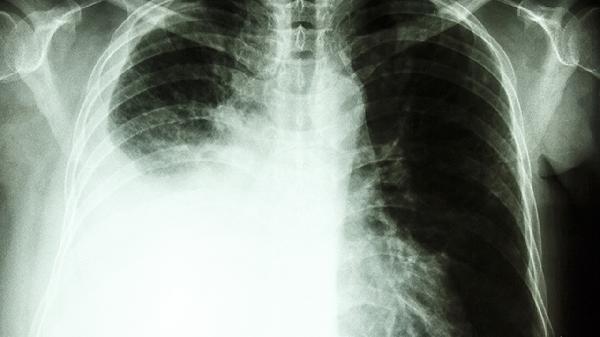

肺结节手术成功率受多种因素影响。对于早期发现的恶性肺结节,通过胸腔镜微创手术切除后五年生存率可达到较高水平。术前通过穿刺活检或影像学检查明确结节性质有助于制定精准手术方案。术中快速病理检查能进一步确认切除范围是否足够。对于直径小于3厘米的孤立性肺结节,完整切除后局部复发概率较低。术后并发症发生率与患者肺功能基础相关,常见并发症包括气胸、肺部感染等,多数可通过规范治疗得到控制。

高龄、合并慢性阻塞性肺疾病等基础肺病患者手术风险相对增加。多发性肺结节或位置特殊的结节可能增加手术难度。部分病例需中转开胸手术完成切除。极少数情况下可能发生术后出血、支气管胸膜瘘等严重并发症。术前全面评估心肺功能、优化合并症管理能有效降低手术风险。术后定期随访复查有助于及时发现异常情况。